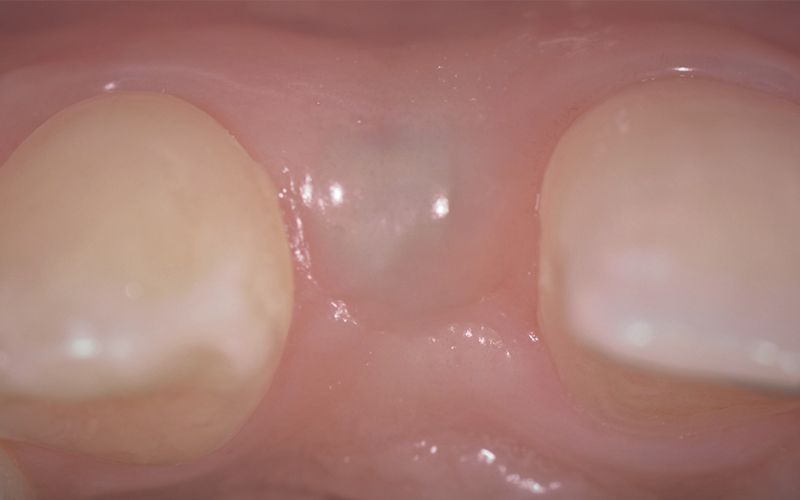

Tras tres meses de osteointegración, se procedió a realizar la segunda cirugía de ambos implantes y se tomaron las impresiones digitales con el escáner intraoral TRIOS (3Shape).

Se mandaron las impresiones a un laboratorio protésicos de confianza para la confección de unos provisionales mientras trabajaban en el diseño y confección CAD-CAM de las coronas definitivas de zirconio.